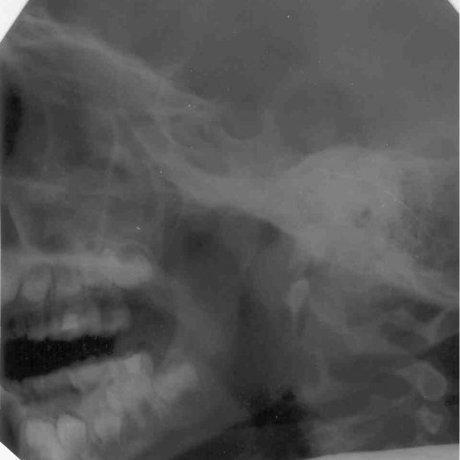

До лечения: у четырёхлетнего пациента аденоиды III степени.

После лечения аденоиды полностью рассосались и носовое дыхание восстановлено.

До лечения: на рентгене мы видим гигантские аденоиды, которые спускаются из носа в глотку. Пятилетний пациент не мог дышать носом.

После лечения носовое дыхание восстановлено и аденоиды рассосались.

Рентгенограммы, подтверждающие эффективность лечения, имеются только в нашей клинике и являются собсвтенностью доктора Сичинава.